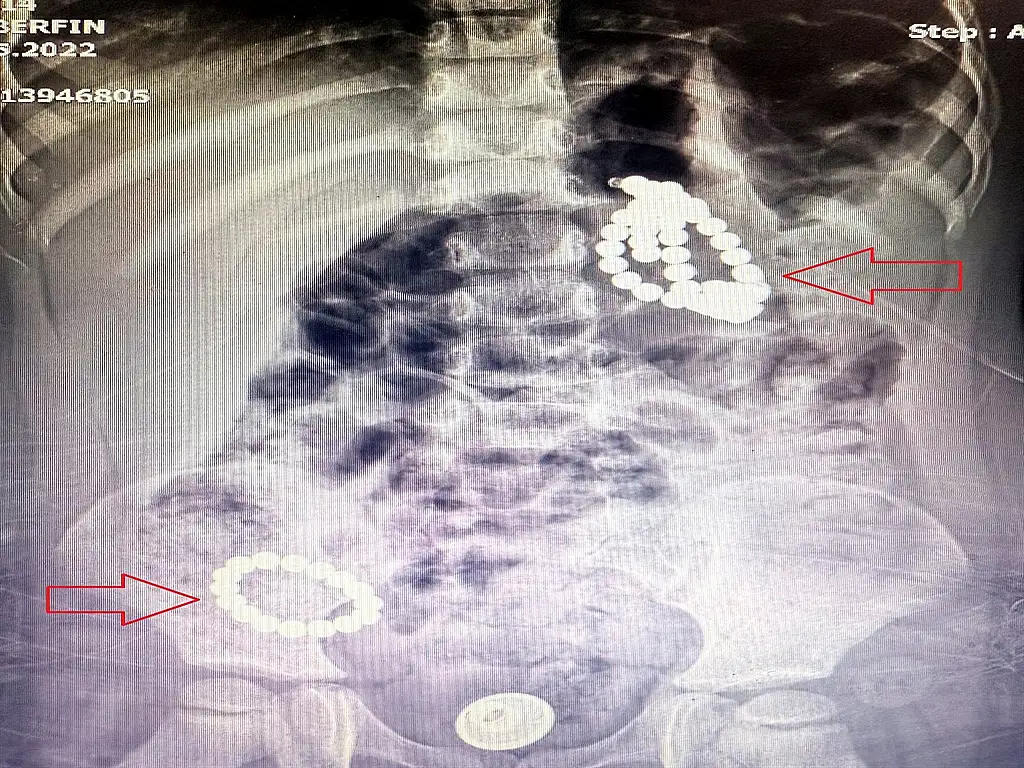

Mahmut ve İsmigül Nesim’in üçüncü çocuğu Berfin, mide bulantısı ve kusma şikayetiyle geçtiğimiz kış hastaneye götürüldü. Mevsimsel salgına bağlı olduğu düşünülerek ilaç tedavisiyle iyileşen küçük kızın ailesi, geçtiğimiz ay şikayetlerin tekrarlaması üzerine bu kez Çam ve Sakura Şehir Hastanesi Acil Servise başvurdu. Çekilen röntgende, mide ve bağırsaklarında boncuk benzeri yabancı cisimler tespit edildi. Aile kızlarının kolye ya da bileklik yuttuğunu düşünürken, doktorlar manyetik boncuklardan şüphelendi. Önce takip edilmek üzere yatışı yapılan çocuğun, yabancı cisimleri dışkı yoluyla atması beklendi. Ancak cisimlerin sabit kaldığı anlaşılınca manyetizma tespit edebilen bir program yardımıyla durumun ciddiyeti anlaşıldı. Yuttuğu cisimlerin mıknatıslı boncuk olduğu anlaşılan Berfin, acilen ameliyata alındı ve Çocuk Cerrahi ve Gastroenteroloji ekiplerinin birlikte girdiği 5 saat süren ameliyatla sindirim sisteminden 66 adet manyetik boncuk çıkarıldı. Endoskopi sırasında midede 3, bağırsaklarda 2 delinme ve yapışıklık da tespit edildi. Edinilen bilgiye göre yaklaşık 7 aydır vücutta bulunduğu düşünülen boncuklar, organları birbirine yapıştırmış ve ciddi hasara yol açtı.Boncuklar çıkarıldı, delinmeler laparoskopik yöntemle onarıldı. Baba Mahmut Nesim, oyuncak olarak satılan boncukların yasaklanması gerektiğini belirtirken, "Bu bir oyuncak değil, ölüm tuzağıymış" diye konuştu.

Minik Berfin’in ameliyatını gerçekleştiren ekipte yer alan Çocuk Cerrahi Uzmanı Opr. Dr. Mehmet Çakmak, "3 yaşında bir kız çocuğu. Acile mide bulantısı kusma şikayetiyle başvurdu. Röntgende, karında çok sayıda boncuğa benzer yabancı cisme rastlandı. Aile daha çok boncuk, bileklik tarzı plastik birşey yuttuğunu düşünüyordu. Görüntüye baktığımızda, son zamanlarda çok sık rastladığımız magnet boncuk yutma vakalarına benziyordu. O yüzden yatış verdik takip amaçlı; fakat yüzde 100 emin olamadık. Plastik ya da taş gibi boncuklar yutulduğu zaman öncelikle takip ediyoruz; ameliyat düşünmüyoruz. Çünkü gaita ile (dışkı) atma olasılıkları oldukça yüksek. Fakat çoklu mıknatıs yutma, acil bir vakadır. Çünkü midede, bağırsaklarda yapışıklıklara ve delinmelere sebep olabilecek potansiyele sahiptir. Bir program vasıtasıyla bunun manyetik bir cisim olduğunu fark ettik ve hastayı ameliyata aldık" dedi.

Ameliyata Gastroentrologlarla beraber girdiklerini anlatan Çakmak, mideden 34 adet manyetik boncuk çıkarıldığını kaydederek sözlerini şöyle sürdürdü: "Endoskopi esnasında midede üç yerde delinme olduğunu gördük. Sonra cerrahi kısma geçtik. Midede, ince bağırsakla birleşmiş halde fistül dediğimiz, yapışıklığa delinmeye bağlı, üç yer tespit ettik. Aynı şekilde ince bağırsakla kalın bağırsağın başlangıç kısmında da iki yerde delinme meydana gelmişti ve bağırsaklar birbirine yapışmıştı. Bunlar çok uzun süreli yapışıklıklardı, yaklaşık 6-7 aydır o manyetik boncuklar midede ve bağırsaklarda birbirine yapışmış halde duruyordu. Toplam 66 tane manyetik boncuk çıkardık. Hastamızın delinmiş organlarını laparoskopik olarak onardık."